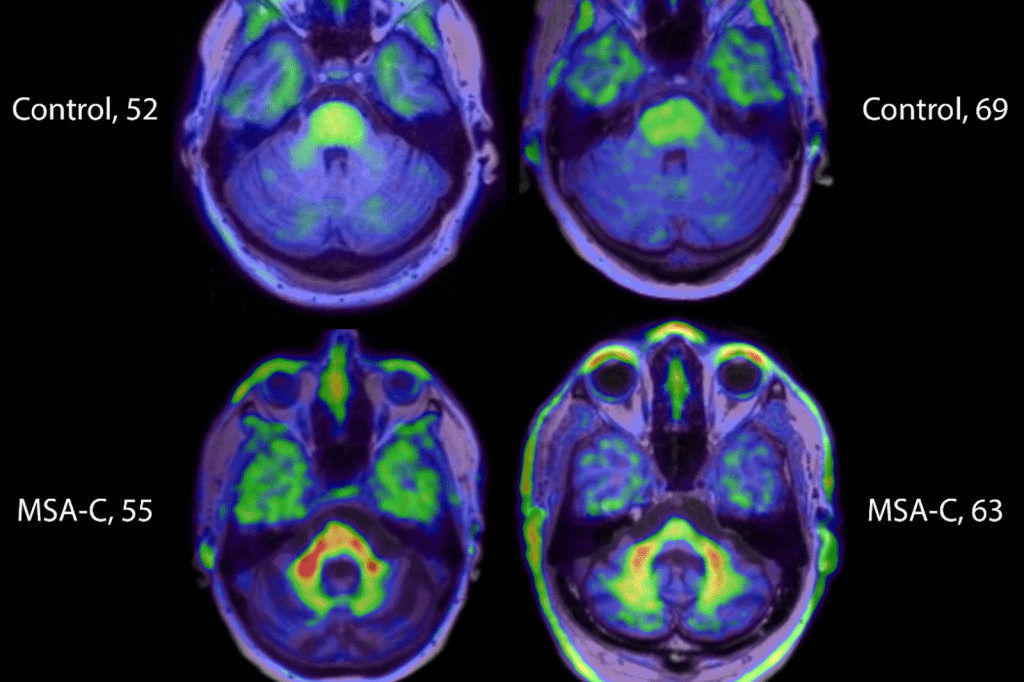

Perfusion SPECT Brain Studies in Anxiety

Perfusion SPECT scans give us a peek into the brain’s blood flow patterns linked to anxiety. This imaging method is key in grasping the brain’s complex workings in anxiety disorders.

Blood Flow Patterns in Anxiety Disorders

Studies reveal that people with anxiety have different blood flow patterns in their brains. Perfusion SPECT lets doctors see these changes. It helps them understand the brain’s inner workings.

Research shows anxiety is linked to more activity in the amygdala and insula. These areas are key for handling emotions and stress.

Regional Cerebral Blood Flow Changes

Looking at regional cerebral blood flow (rCBF) changes is a big part of perfusion SPECT studies in anxiety. It helps researchers spot which brain areas are impacted by anxiety.

- More rCBF in the amygdala and anterior cingulate cortex is tied to higher anxiety.

- Less rCBF in the prefrontal cortex might mean trouble with emotional control.

- The type of anxiety and the person’s symptoms can affect rCBF changes.